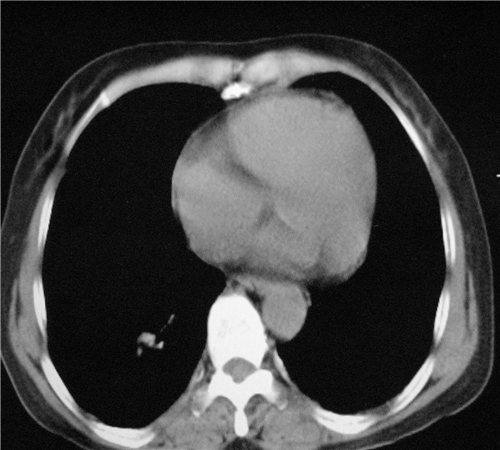

标题: CT26849:女67岁反复胸痛两天余,临床考虑夹层。 [打印本页]

标题: CT26849:女67岁反复胸痛两天余,临床考虑夹层。

右肺感染,未见夹层。

升主动脉增宽是怎么回事啊!食管有事吗?老师

既然考虑夹层,建议强化!另:右下肺感染!

1)右肺感染性病变。2)建议行ct增强扫描或mri检查排除主动脉夹层。

双下肺感染,右侧显著。有无夹层,增强扫描后再诊断。

1. 感染性病变,2.未见夹层,3.食道未见异常。

平扫未见确切夹层征,建议必要时增强扫描或mri检查。